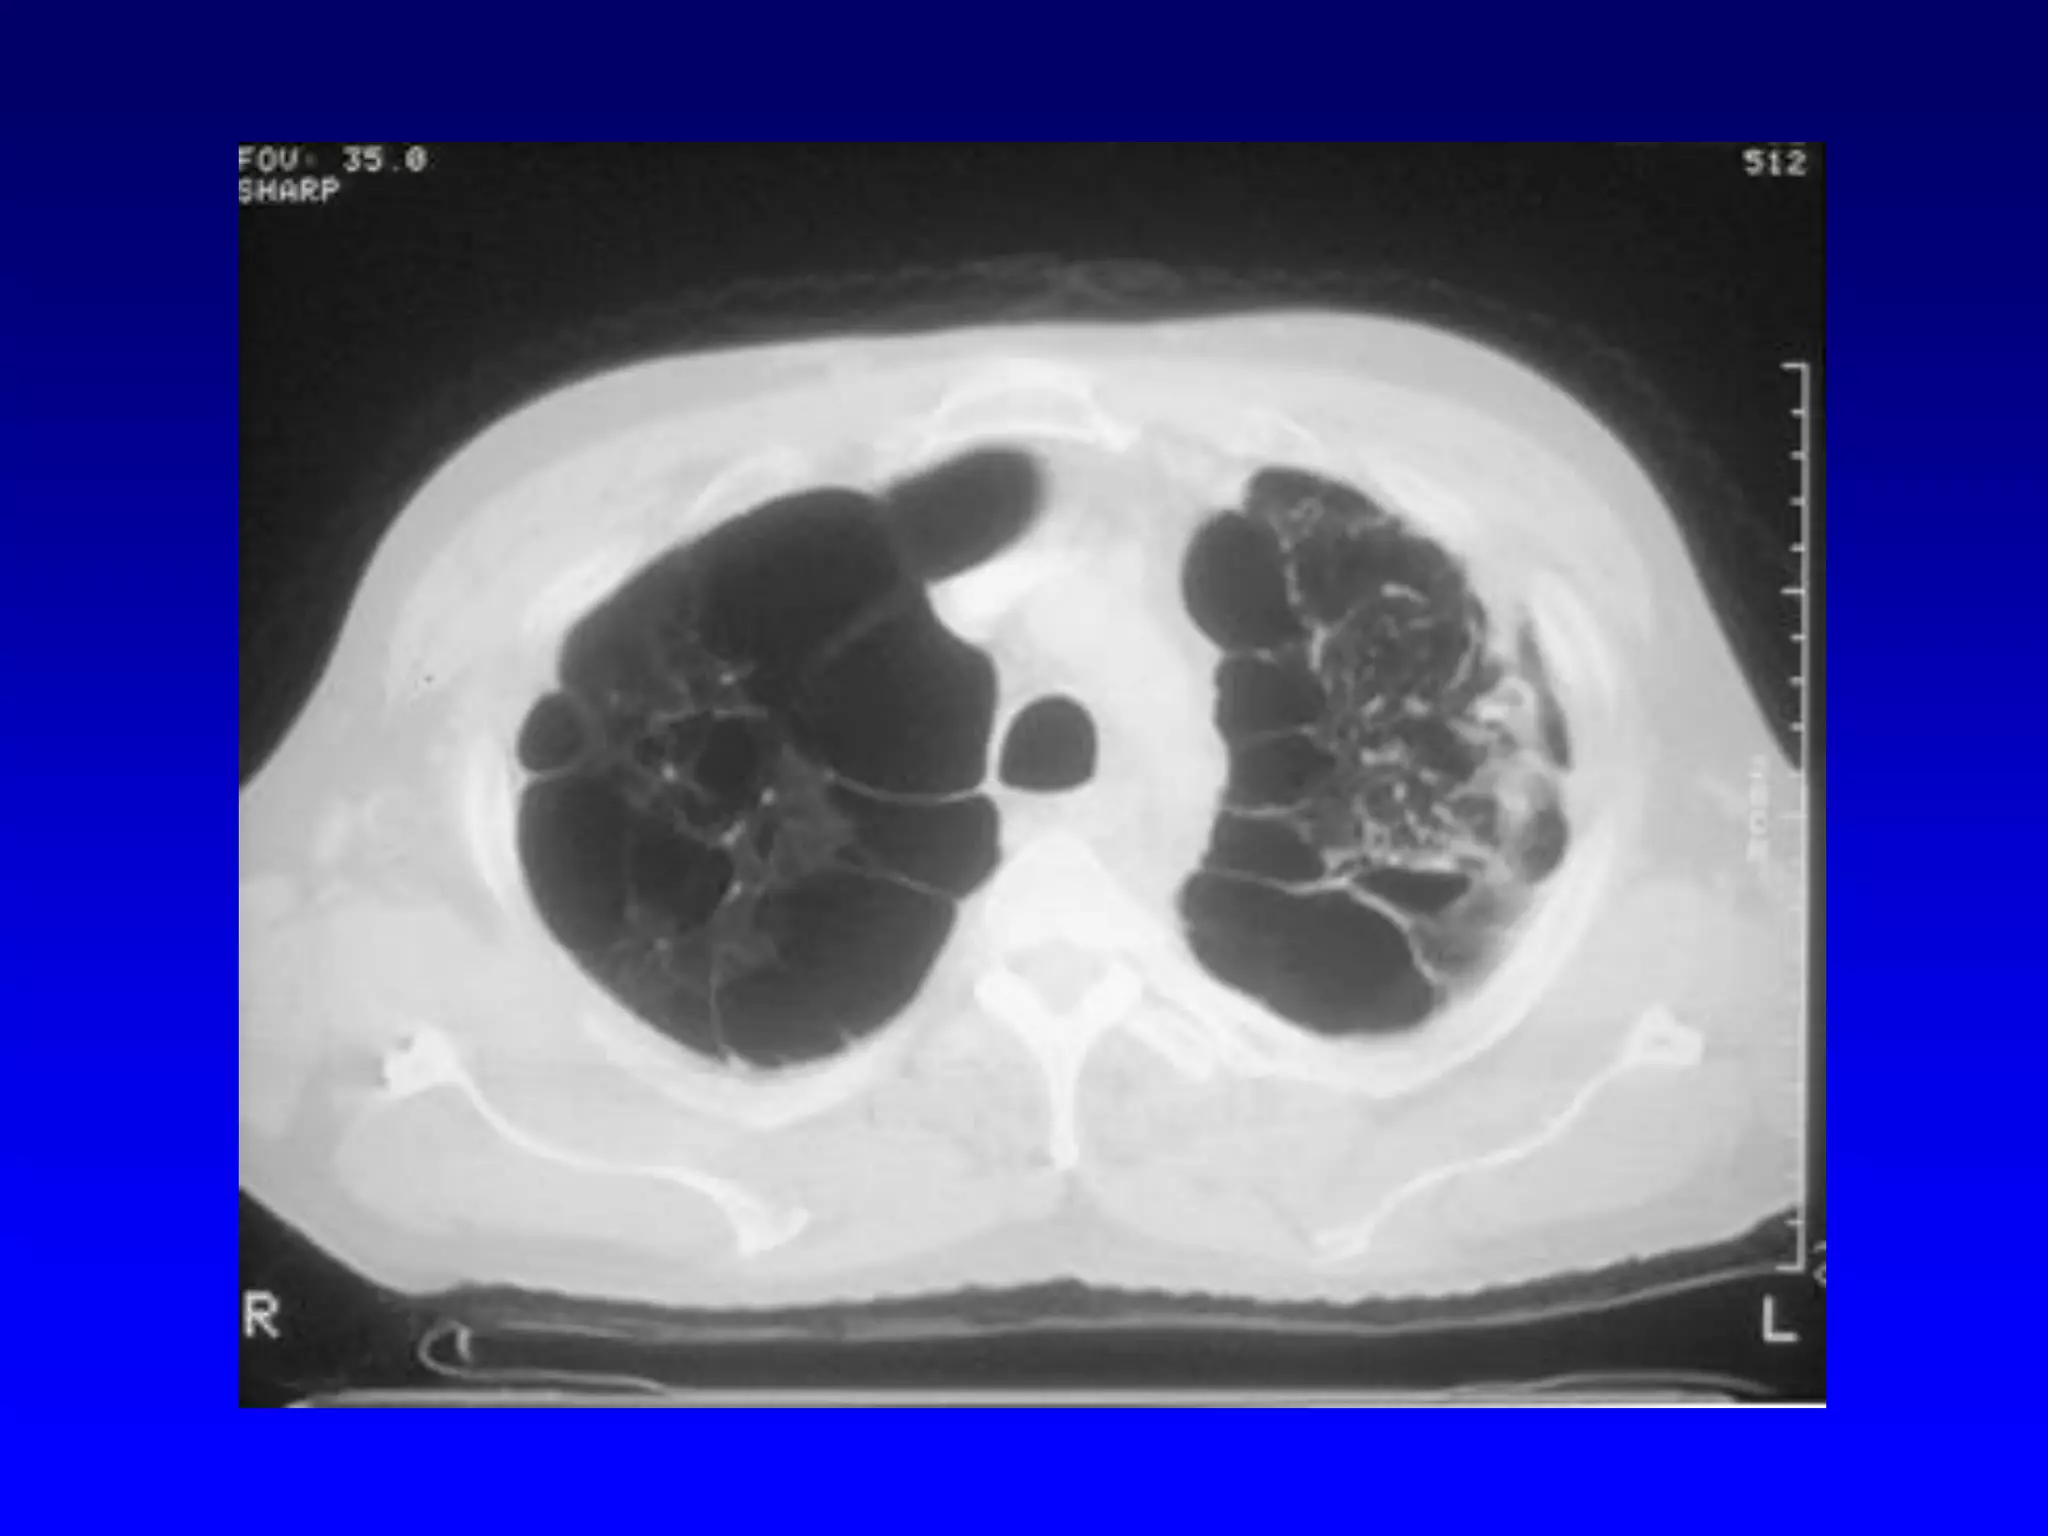

Sub-segmental Atelectasis

Atelectasis

Segmental

Anterior sub-segment of RUL

"Bronchial wedge"